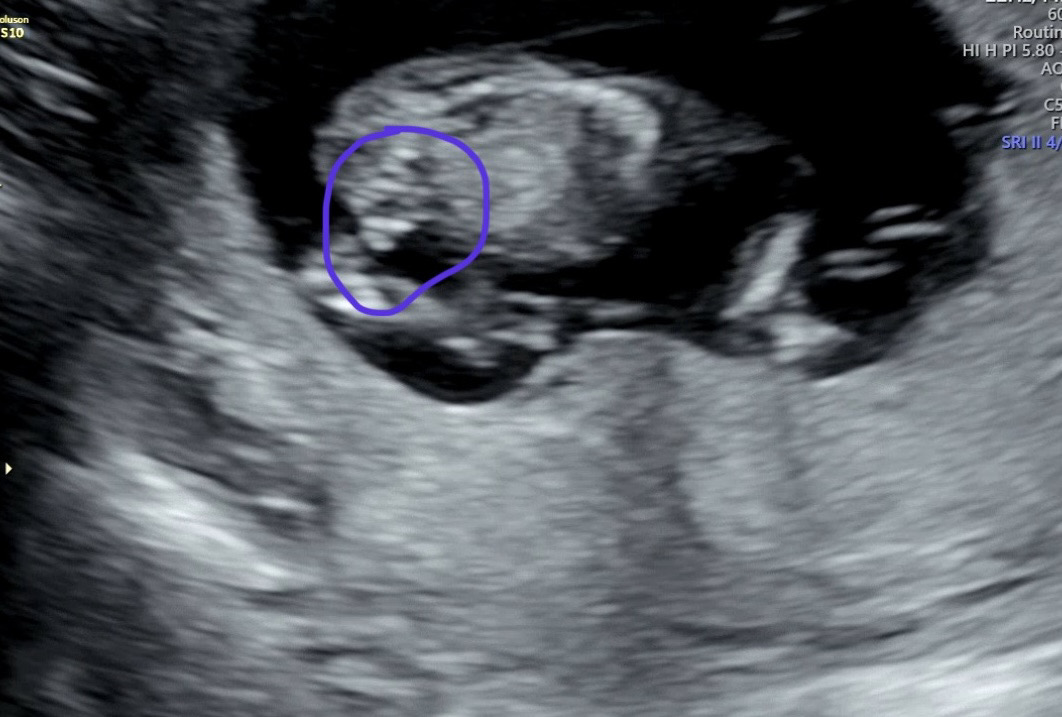

13주 1일차 초음파 봐주세효,, ㅠㅠ

선배님들 오늘 13쥬 1일차로 초음파 보고왔는데 저거 꼳츄 인가요,,,? 생식기 부분 밑에서는 안 찍어주시던데 그건 아기가 움직여야 볼 수 있는건가요??